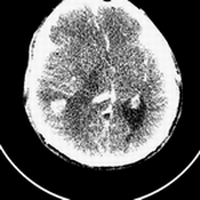

标题: CT25808:男,48岁,头痛多年,近段时间头痛加重伴步态不稳 [打印本页]

标题: CT25808:男,48岁,头痛多年,近段时间头痛加重伴步态不稳

平扫:右颞顶叶病灶呈等低密度伴大面积水肿,脑室受压变形。增强:病灶显著强化。考虑淋巴瘤或黑色素瘤。

1)不排除黑色素瘤可能;建议行mri检查。2)大脑镰下疝。3)脑积水(梗阻性)。